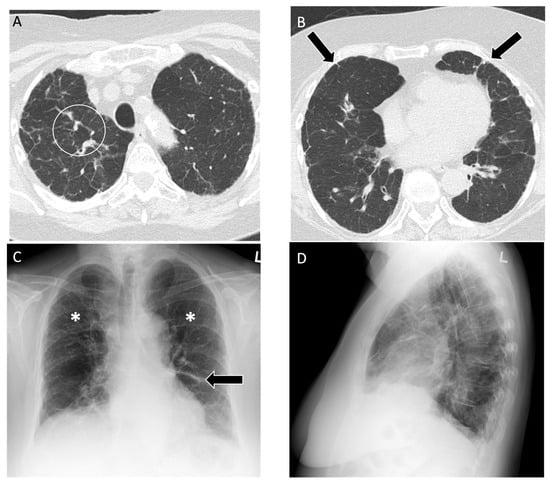

Figure 9.

A 76-year-old non-smoking female was diagnosed with farmer’s lung, proven with biopsy. Computed tomography of the upper lobe demonstrates (A) peribronchovascular reticulations (white circle) with mosaic lung attenuation and (B) mild diffuse subpleural reticulations (black arrows); (C) posteroanterior and (D) lateral view radiographs demonstrate diffusely coarse reticulations and fibrosis (asterisks) in the upper lung zone with some mild volume loss. A staple line in left lower lobe is noted from a previous lung biopsy for diagnosis of farmer’s lung disease (black arrow).